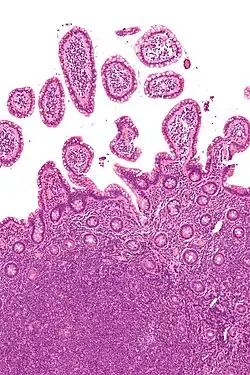

| Micrograph of mantle cell lymphoma, a type of non-Hodgkin lymphoma. Terminal ileum. H&E stain. | |